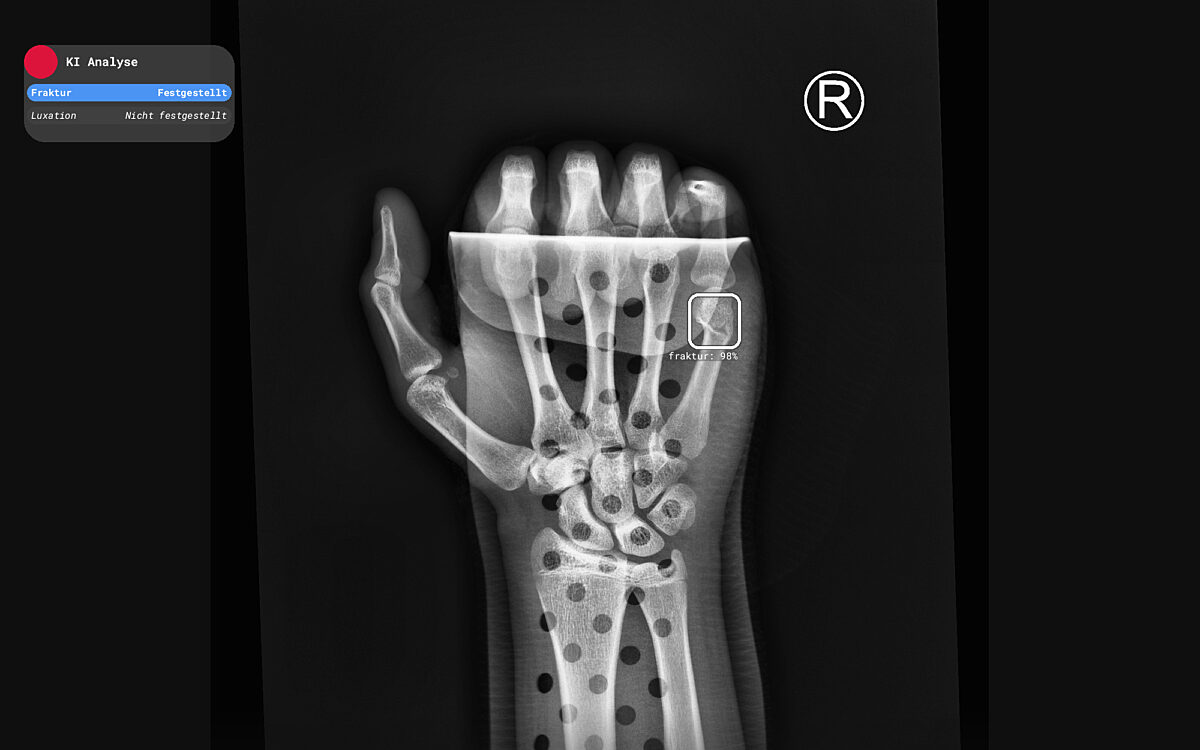

Quelle: Hand-Fraktur_©RBfracture™-by-Radiobotics

GELNHAUSEN. Die Main-Kinzig-Kliniken setzen jetzt Künstliche Intelligenz in der Notaufnahme ein. In einer Pressemitteilung geben sie bekannt, dass die KI-Software Knochenbrüche und Verrenkungen erkennen soll. Dazu werden die Röntgenaufnahmen analysiert. Ganz fehlerfrei ist das System allerdings nicht, deshalb wird es derzeit nur zur Ersteinschätzung genutzt. Die endgültige Diagnose soll weiterhin von einem Radiologen getroffen werden.